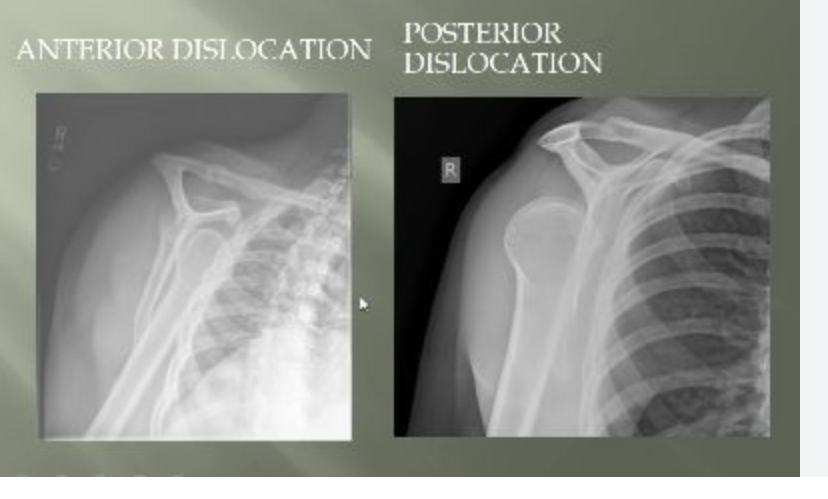

Dislocation

when bones at a joint separate from their normal positions, often caused by trauma, leading to intense pain, swelling, deformity, and inability to move the joint